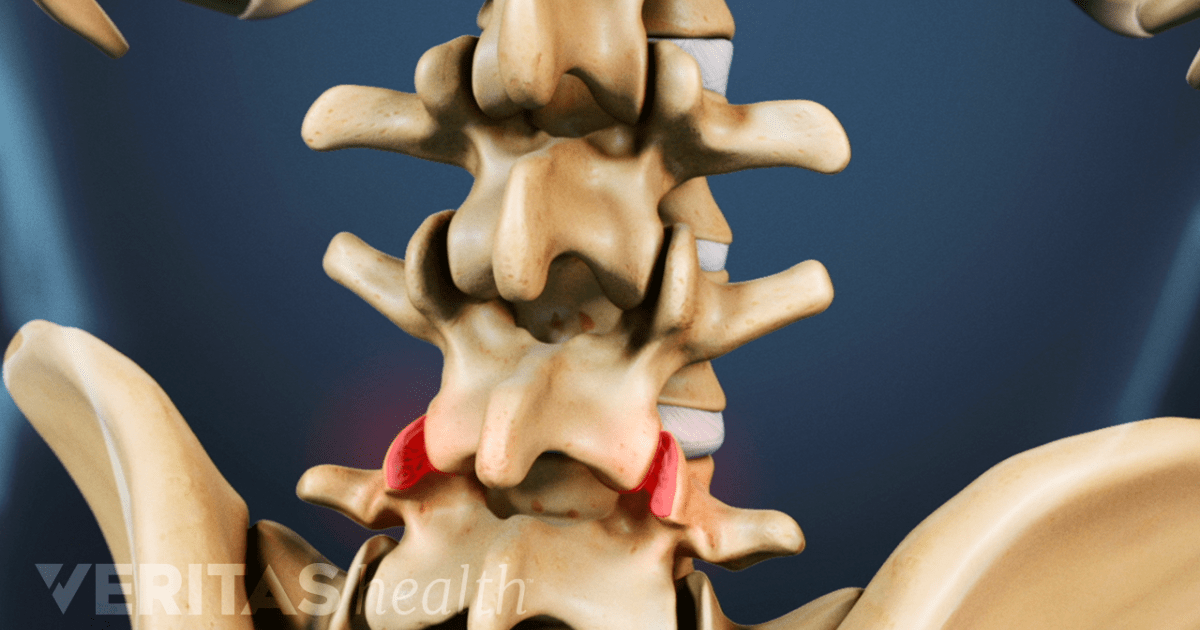

Spine Osteoarthritis Market: Recent Growth Activity have Created Attractive Opportunity

A new business intelligence report released by Advance Market Analytics with title “Global Spine Osteoarthritis Market Insights, Forecast to 2025” has abilities to raise as the most significant market worldwide as it has remained playing a remarkable role in establishing progressive impacts on the universal economy. The Global Spine Osteoarthritis Market Report offers energetic visionsContinue reading “Spine Osteoarthritis Market: Recent Growth Activity have Created Attractive Opportunity”